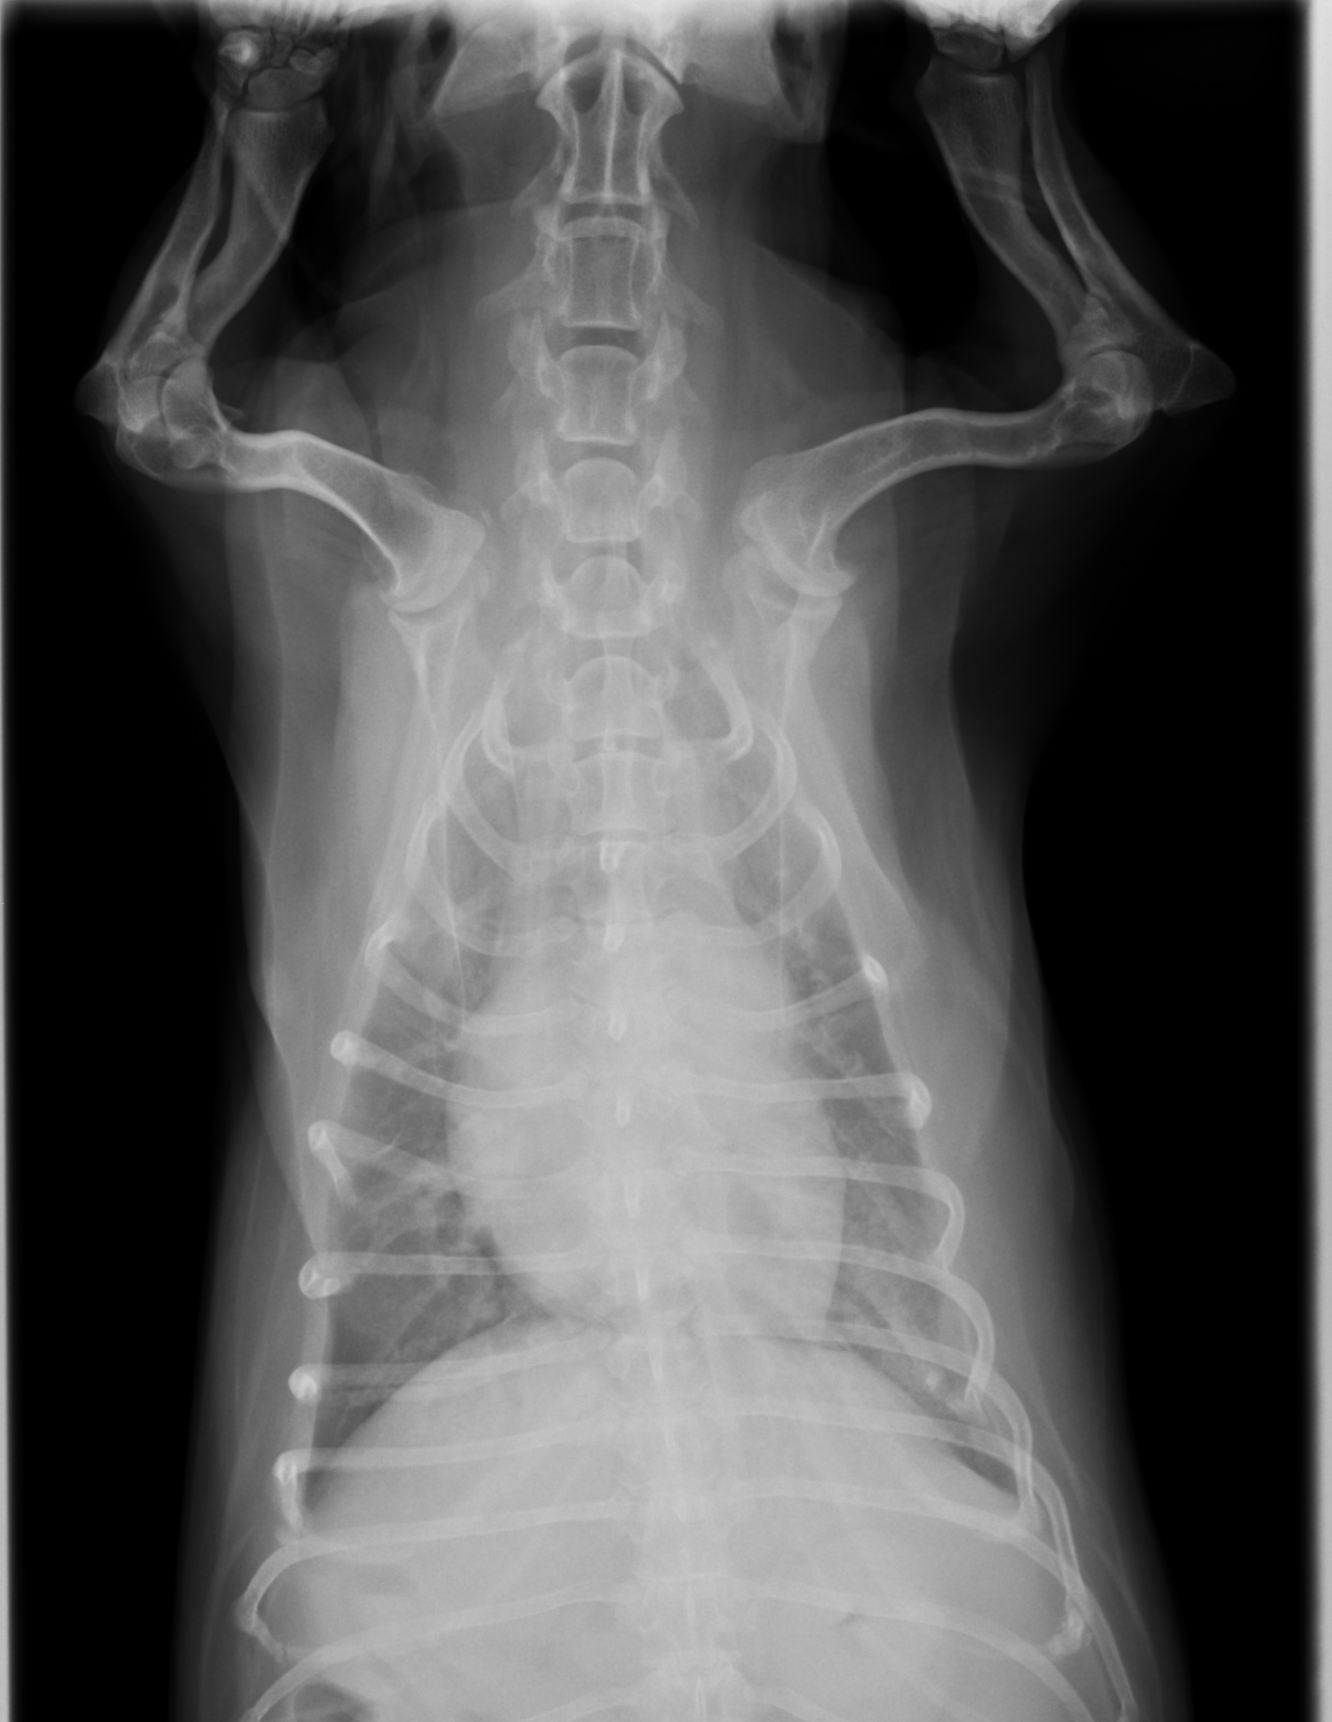

身体的検査、レントゲン検査、血液検査などから総合的に診断します。 聴診器を使って肺の音を聴診します。肺炎の場合、みずっぽいような音やゴロゴロとした異常な音が聞こえることがあります。レントゲン検査では胸部のレントゲンを撮影します。肺炎の場合、肺が白く見え、気管支が白くはっきり見えるようになります。また、左右の肺の前葉や右側の中葉といった一部の肺野が白くなっていると誤嚥性肺炎を疑います。血液検査では白血球の増加や、炎症の指標であるCRPの上昇が見られることがあり、感染の有無や炎症の程度を評価します。

レントゲン画像